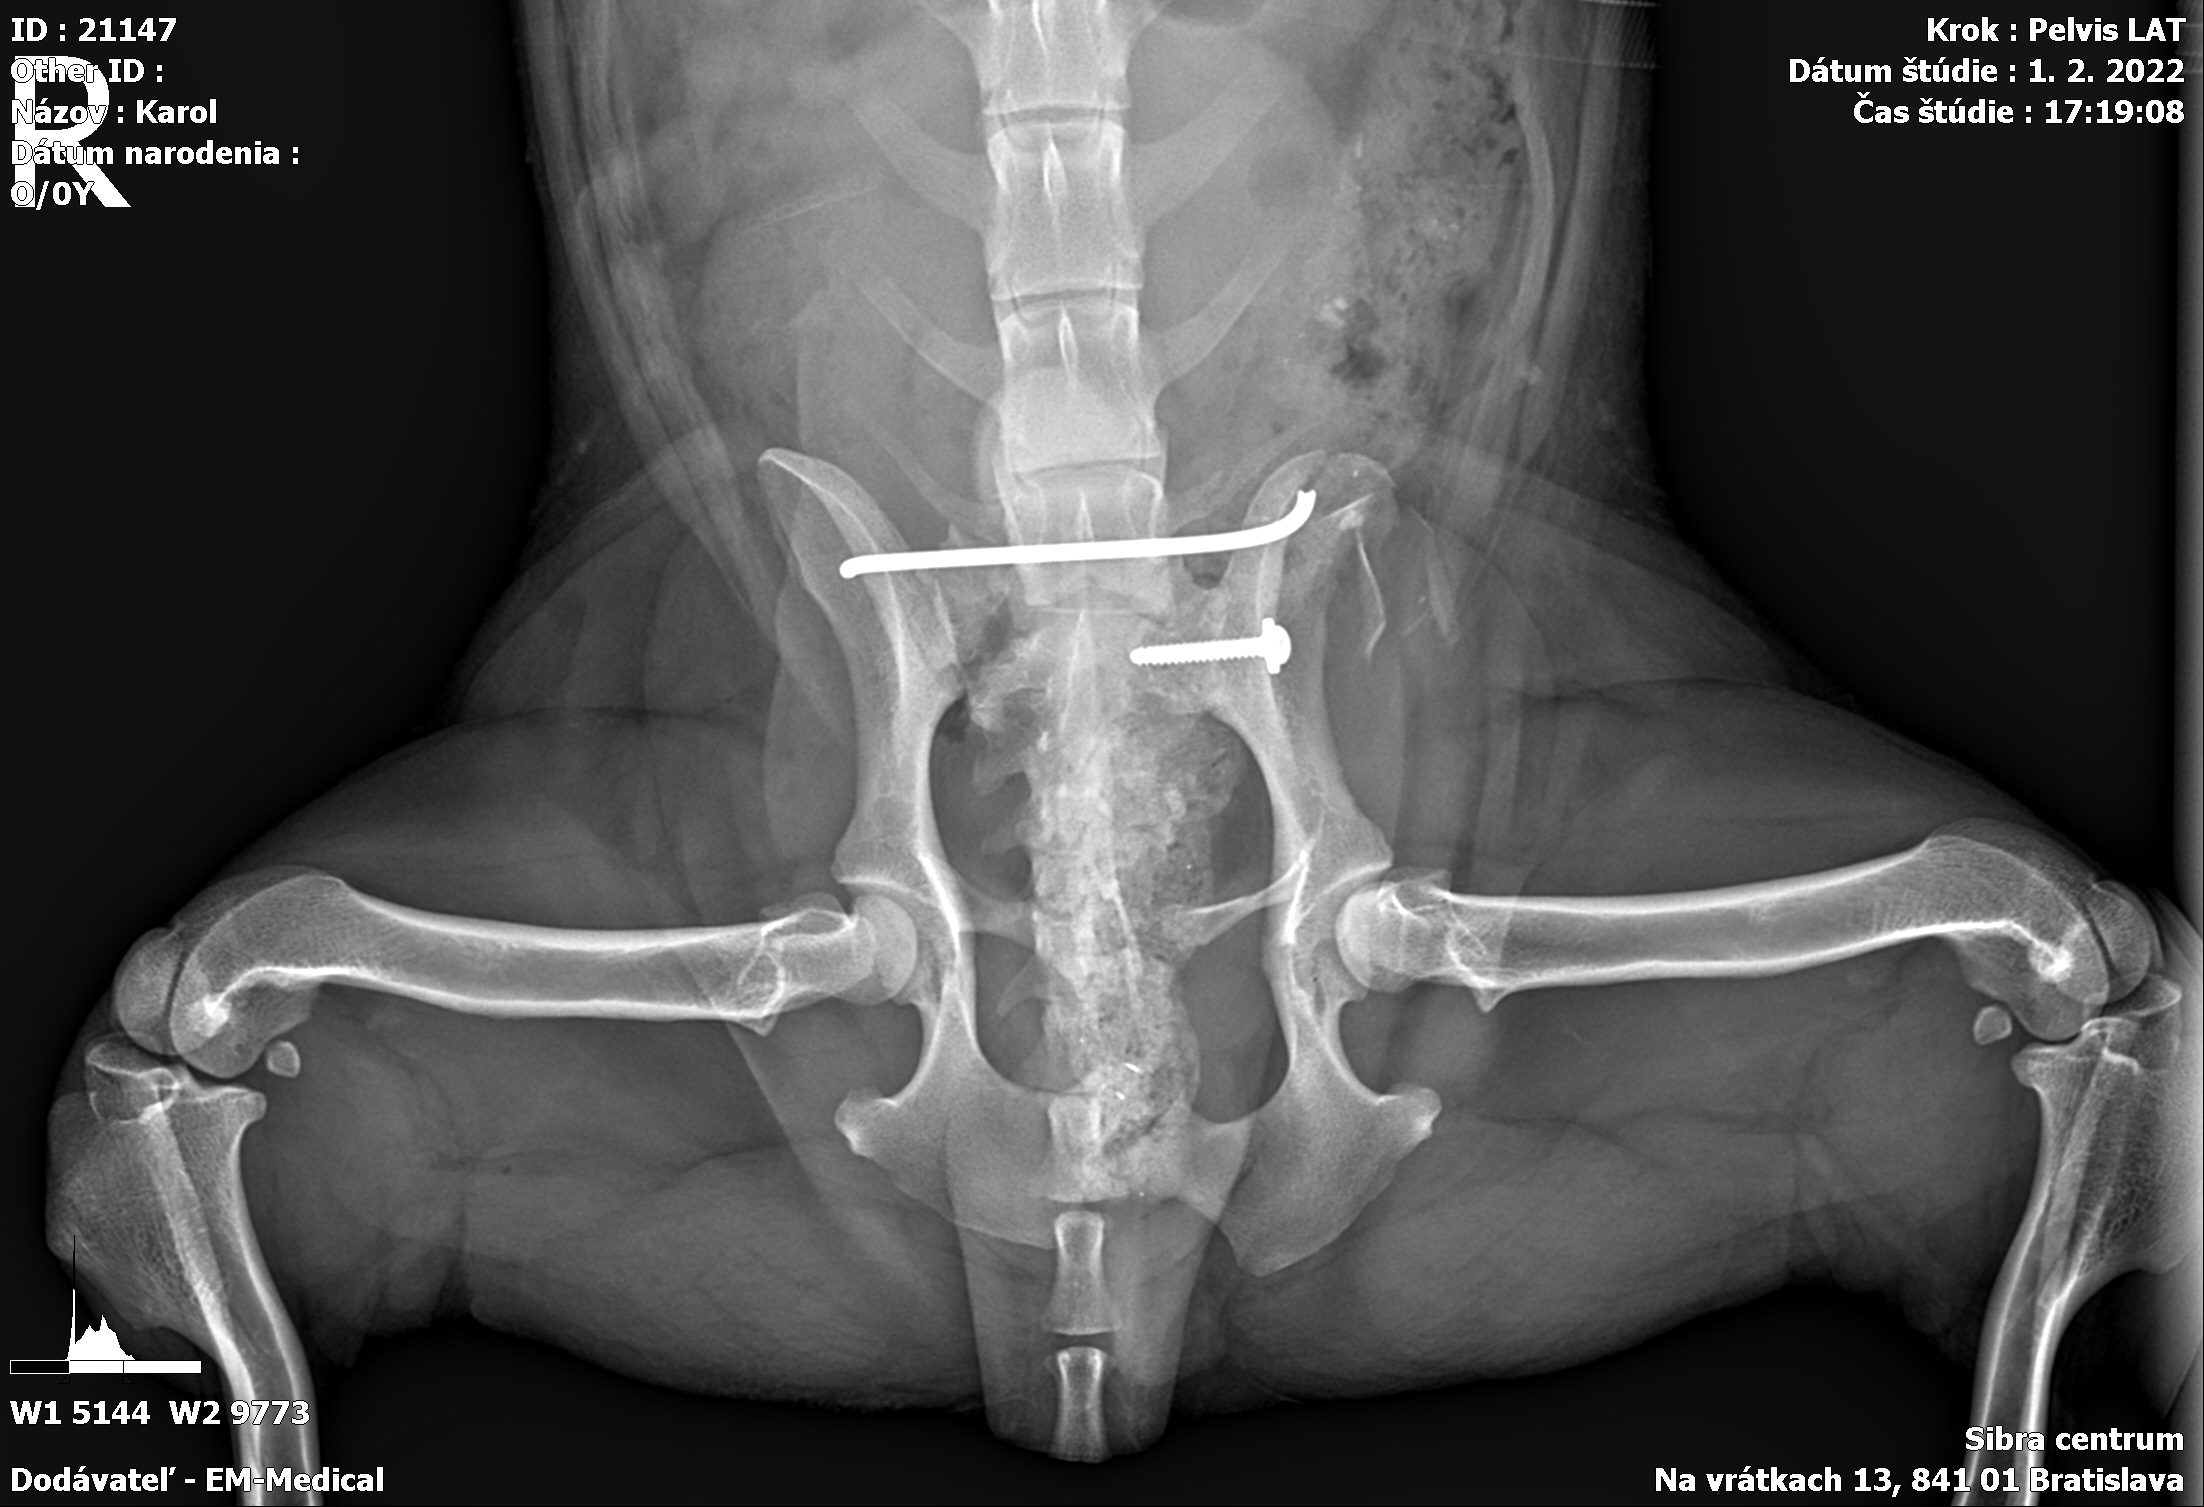

Karola nám doviezla pani, ktorá ho našla, asi jediná dobrá duša, ktorá pri ňom neprešla so zatvorenými očami. Ihneď sme s krpcom utekali na veterinu aby sa zistila závažnosť jeho zranení. Hneď pri prvých RTG snímkoch sa ukázala obojstranná fraktúra panvy, taktiež fraktúra krídla panvy a keby mu to chudákovi nestačilo, do tretice sa objavila zlomenina stavca. Karolko mal neznesiteľné bolesti, ale krásne prečkal vyšetrenie lebo vedel, že je v dobrých rukách a dostáva sa mu pomoci. Po nálezoch sme okamžite kontaktovali neurológiu a ortopédiu na veterinárnej klinike Sibra - centrum veterinárnej medicíny, kde sme dostali hneď termín na príjem.

Karol nemá žiadne neurologické deficity, po ortopedickej operácii bude vedieť behať a bez problémov bude vedieť samostatne cikať a kakať. Po tejto úžasnej správe sme samozrejme dali zelenú náročnej ortopedickej operácii pod vedením MVDr. Vatolíka. Operácia sa podarila na výbornú, Karči je "zoskrutkovaný" a vôbec nič mu nebráni v tom, aby opäť mohol behať a aktívne žiť. Momentálne sa zotavuje po operácii, musí mať prísny kľudový režim. Po vybratí stehov ho čaká hydro- a fyzioterapia, ktorá mu pomôže postaviť sa na nohy. Je to bojovník, veľmi sa chce uzdraviť a v jeho očkách je dokonale vidieť, že už kuje plány čo všetko zameškané bude musieť dobehnúť.